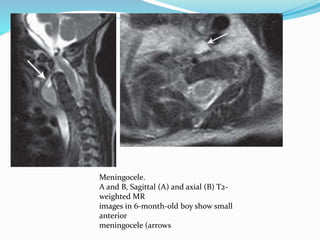

Meningocele.

A and B, Sagittal (A) and axial (B) T2-

weighted MR

images in 6-month-old boy show small

anterior

meningocele (arrows